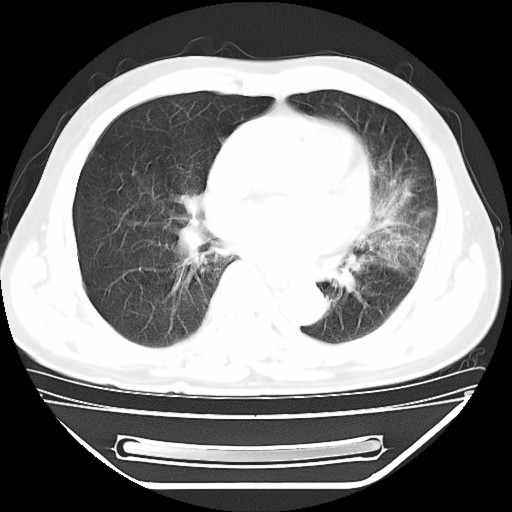

以下是引用hhcckk在2009-5-29 10:34:00的发言:[br]左下肺片絮状边缘模糊影,考虑感染,建议治疗后复查[br]